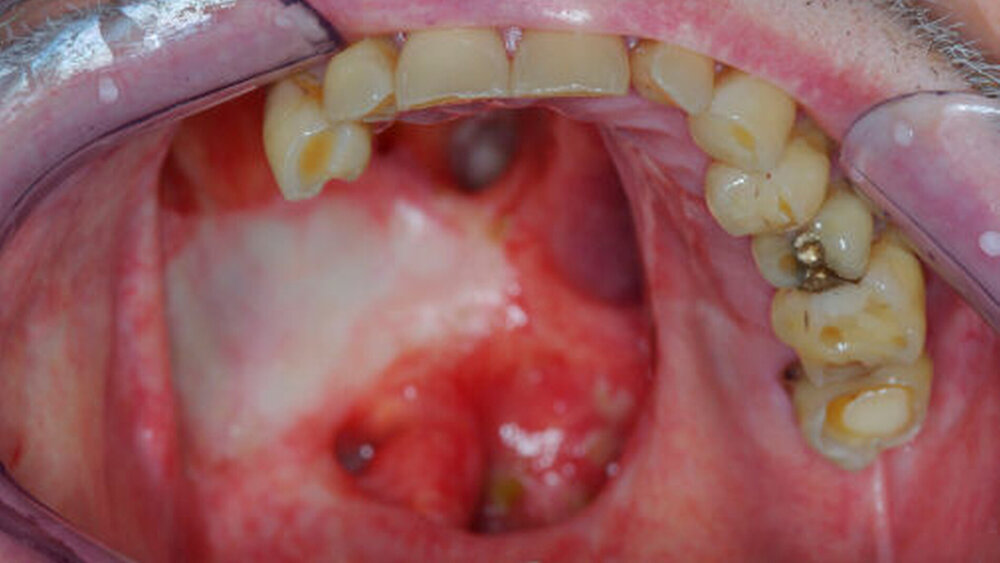

Das Verzeichnis bezieht sich in erster Linie auf Behandlungsorte, an denen intraorale defektprothetische Versorgungen durchgeführt werden. Falls auch extraorale Behandlungen durchgeführt werden, ist dies extra vermerkt. Für die Suche nach rein epithtetischen Behandlungsorten wird auf die Website desDeutschen Bundesverbandes der Epithetiker e.V.verwiesen.